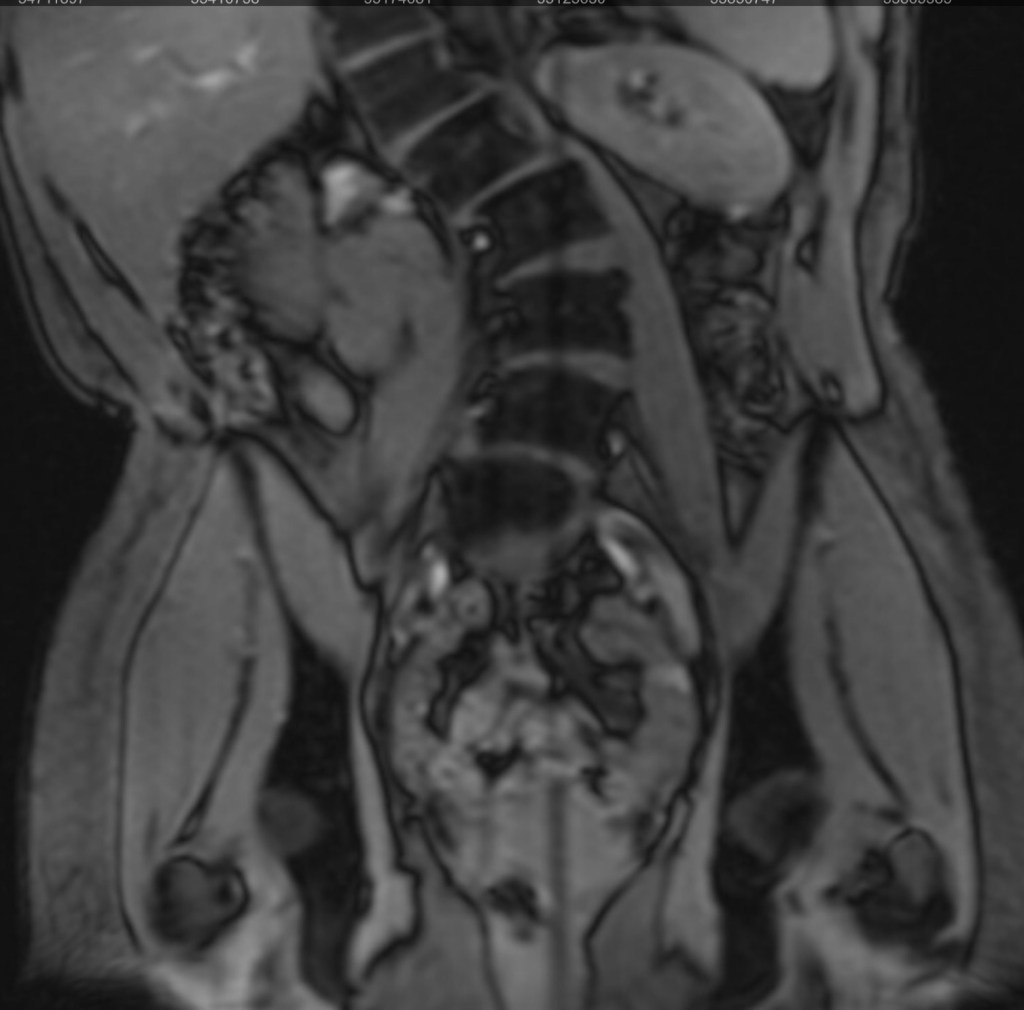

At my 3-month post-op appointment, my surgeon lifted all my restrictions and said I can return to all activity, “just listen to [my] body.” She measured my X-rays (above) and said my lumbar curve decreased 20 degrees, and the thoracic is the same. Also, I grew half an inch. I showed her the scoliosis program I found in New Hampshire, and she was all for it. I’ve booked a furnished apartment in New Hampshire 4/20-5/31 and scheduled the 12 sessions of treatment at the PT clinic there. I’m hopeful that will help with my back pain, and maybe even reduce my thoracic curve. And right before that, I’ll be attending Bionicon!

I’m walking without the cane and my balance feels back to how it was pre-surgery. My hip pain is still gone, but my low-back pain is where it was pre-surgery. The pain in my ribs is still intense. I wake up with my pain at a 4-5 and by the end of the day it’s an 8-9. The pain matches the compression you can see from these pics (morning on the left, bedtime on the right).